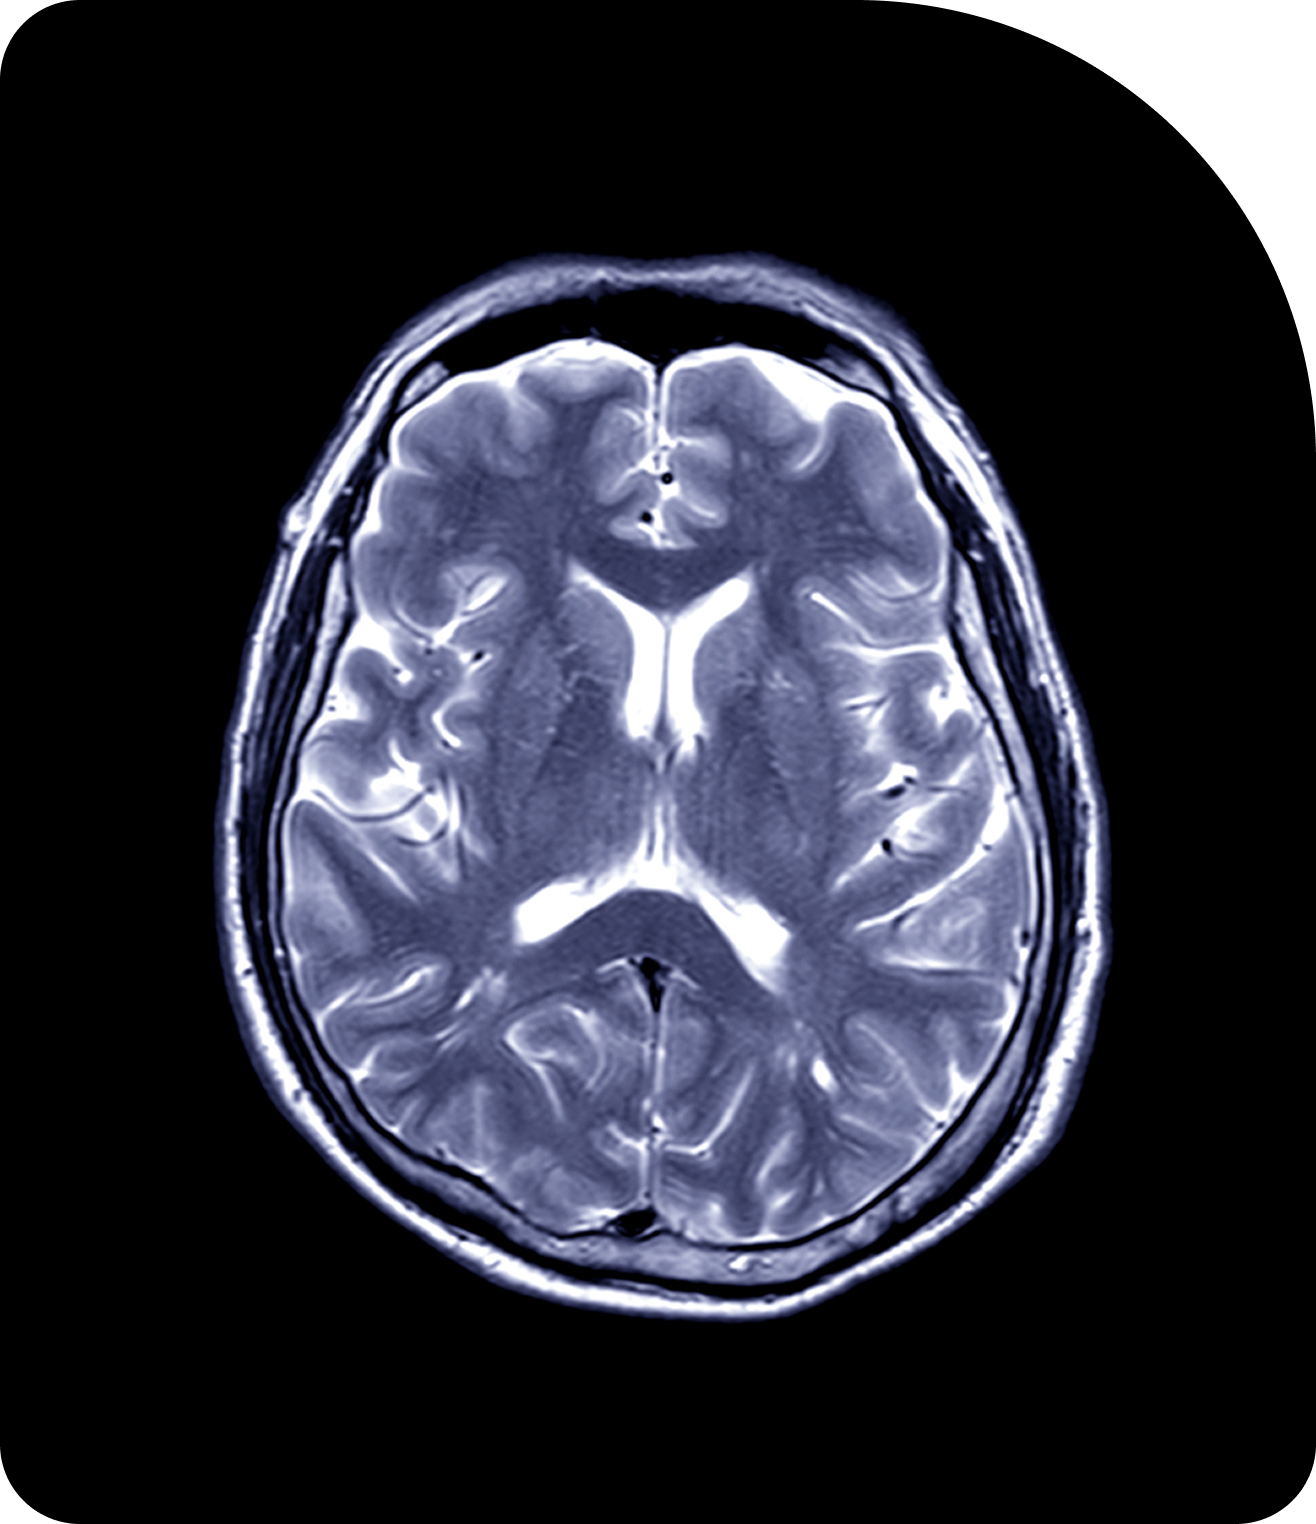

Compare Imaging TechnologiesAdaptive Radiotherapy in Action

Key clinical trials highlight Adaptive Radiotherapy’s feasibility, safety, and efficacy across tumor sites.

The evidence base to date underscores Adaptive Radiotherapy’s transformative potential in multiple disease sites. Across gynecologic, brain, prostate, liver, and head & neck cancers, Adaptive Radiotherapy consistently enables personalized treatment, improved local control, and reduced toxicity.